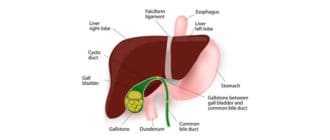

胆嚢は、腹の右側に位置する梨状の消化器系器官である。その仕事は、脂肪消化のために胆汁を貯蔵し、放出することである。 肝臓への接続(ダクト)が「石」によってブロックされた場合、胆汁はバックアップされ、胆嚢に炎症を起こす(急 […]